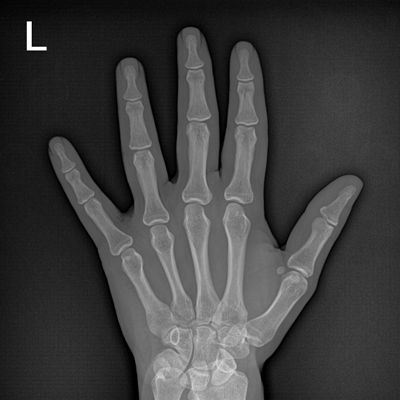

用于影像科、急診室、病房、ICU、手術(shù)室等多場(chǎng)景應(yīng)用。

● 數(shù)字化無(wú)線平板成像,操作簡(jiǎn)便,成像質(zhì)量高